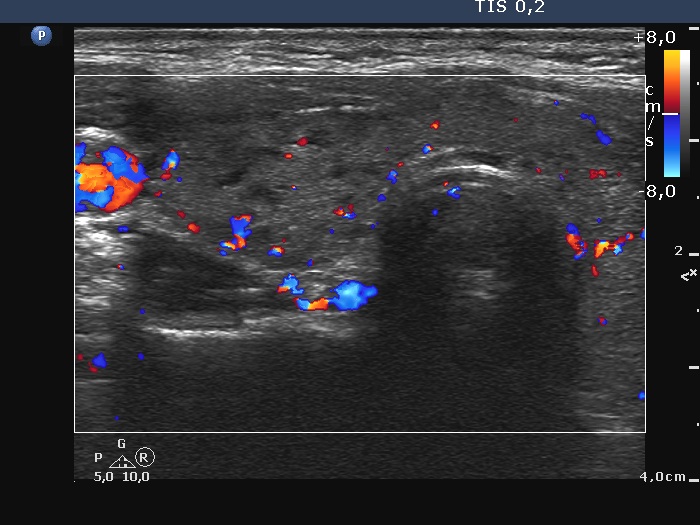

Second examination - five years later (second row of images)

Clinical presentation: The patient came to follow-up because she noticed a slow increase in the size of the left lobe.

Palpation: a firm nodule in the left lobe.

Laboratory tests: TSH 0.98 mIU/L.

The dimensions of the nodule in the left lobe were 40x25x43 mm, width, depth, length, respectively, the volume of the lesion was 22.5 mL.

Aspiration cytology resulted in follicular tumor. Surgery was advised.